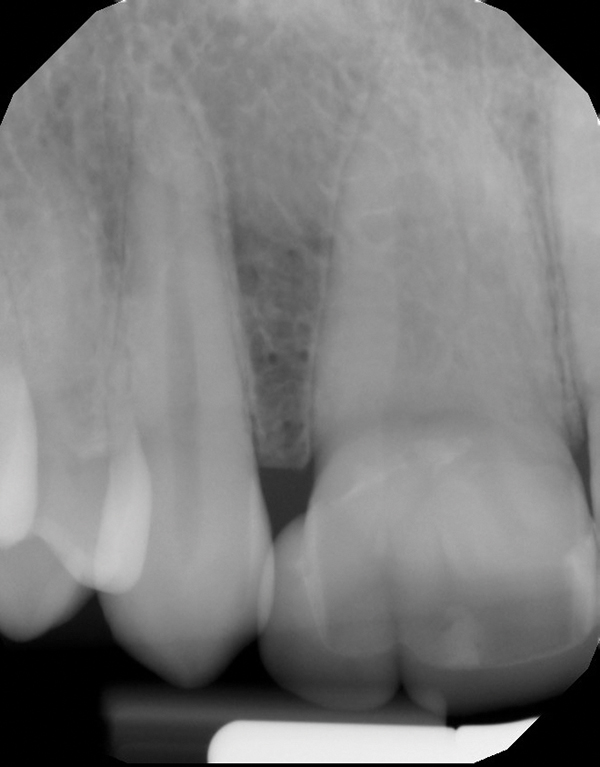

Fig 3. Radiographic scan of fused maxillary central-peg lateral incisors, teeth Nos. 7 and 8, and congenitally missing lateral incisor, tooth No. 10.

Figure 3

A 9-year-old girl, referred to a prosthodontic office by her pediatric dentist, presented with her mother’s chief complaint: “The kids are teasing her about her big front tooth.” Findings from radiographic and clinical examinations revealed fused maxillary central-peg lateral incisors, teeth Nos. 7 and 8, and a congenitally missing lateral incisor, tooth No. 10 (Figure 1 through Figure 3). An implant was selected as the ideal treatment to replace tooth No. 10 when somatic growth was complete. A diagnostic wax-up was fabricated to determine if the fused tooth could be made to resemble two teeth, using pink composite to give the illusion of an interproximal papilla. The patient was referred for an orthodontic consultation to plan for closure of the diastema between teeth Nos. 8 and 9 and achievement of proper alignment for implant No. 10. The patient was also referred to a periodontist for pretreatment assessment of the tooth No. 10 site. An endodontist was consulted should exposure of the large pulp occur during tooth preparation.